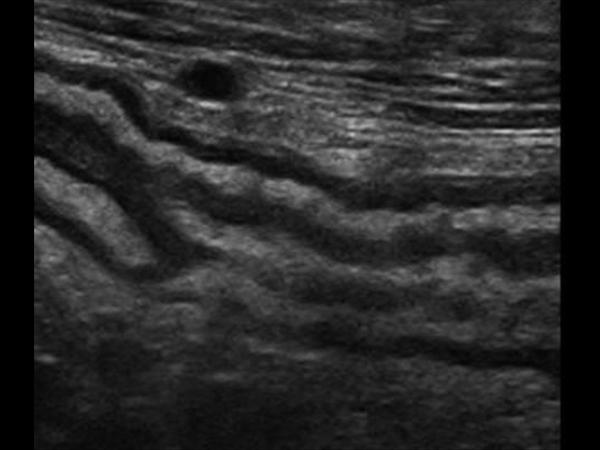

Viêm đại tràng

» Thông tin: Nam giới – 41 tuổi.

» Lâm sàng: Đau hạ vị.